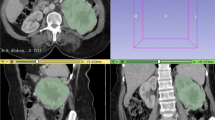

Images obtained in the unenhanced, late arterial, venous, and delayed phases were used for the texture analysis. For each patient, a volume of interest (VOI) of the whole lesion for each phase was selected by means of manual segmentation (Fig. 1) by one radiologist with 15 years of experience in adrenal imaging (C.M.). The feature extraction was carried out using the LIFEx software [16]. Both first-order and second-order features were analyzed. First-order features are extracted evaluating the mean, skewness, and kurtosis of the distribution of Hounsfield Units (HU) of the voxels in the VOI, as well as geometrical features of the lesions such as compacity or sphericity of the VOI. Second-order features are derived from matrixes, calculating, for each voxel in pair with the adjacent ones, indices such as homogeneity, contrast, correlation, entropy, and dissimilarity for the grey-level co-occurrence matrix (GLCM) [16, 17]. This approach was purely explorative and not prognostic; thus, no derivation and validation cohorts were planned.

Cluster analysis